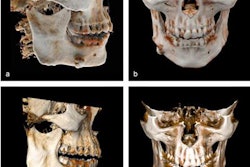

(A) Panoramic radiograph reveals needle fragment located at the anterior ramus of the left mandible. (B) A CBCT image of the lost needle, with two injection needles used as reference points.In this case, the man's dentist referred him to the maxillofacial and oral surgery department to have a suture needle removed from his left buccal mucosa. The needle was supposed to be tied with nylon, but the dentist cut it while performing explantation and local flap surgeries due to the man's chronic peri-implantitis, they wrote.

During an oral exam, a surgeon inserted two needles perpendicularly into the man's left buccal mucosa as reference points to better locate the lost suture needle. Then, the patient underwent a CBCT scan that revealed the broken needle was located above the injection needle and below the maxillary tuberosity, the authors wrote.